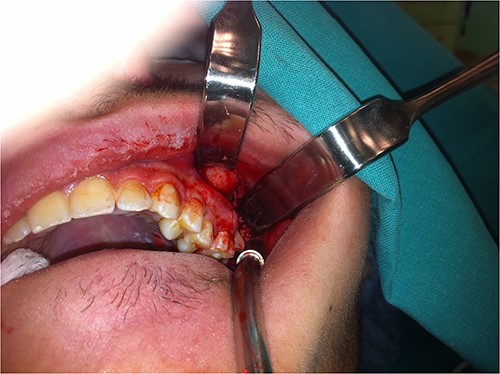

The patient was operated under general anesthesia for better comfort both for the patient and for the surgeon. After local anesthesia with vasoconstriction (lidocaine with adrenaline 1:100 000), an incision was made along the upper buccomaxillary sulcus (Fig. 3). With careful blunt tissue dissection, the crown of the tooth was revealed. With meticulous manipulations to avoid upward displacement of third molar, the tooth was grasped firmly with long Adson forceps and removed (Fig. 4). After copious irrigation of the surgical field, the wound was closed with interrupted resorbable sutures. Pre-operative CT imaging was proved valuable for finding the precise location of the displaced tooth during the operation and avoiding more cumbersome approaches. The surgical procedure lasted about 10 min.

Photograph showing the intraoral approach to the infratemporal fossa through a long incision into the bycco-gingival sulcus.